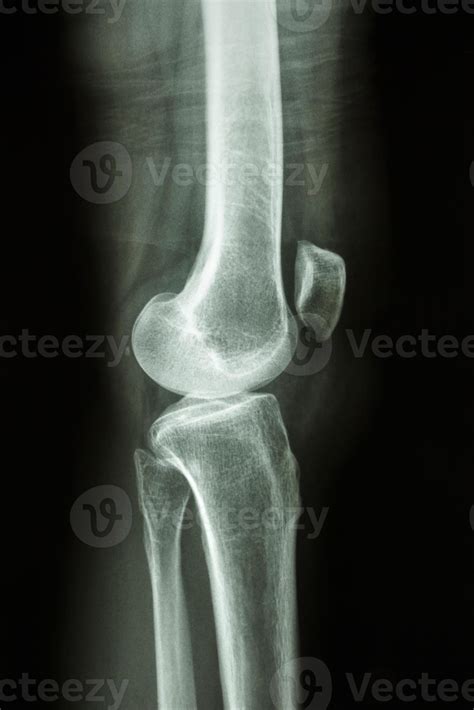

When experiencing persistent joint pain or following a traumatic injury, medical professionals often order specific diagnostic imaging to visualize the complex anatomy of the human leg. Among the most common and essential examinations is the Lateral Knee Xray. This specific projection is critical for clinicians to view the knee joint from the side, allowing for a precise evaluation of the patella, the joint space, and the relationship between the femur and the tibia. Understanding why this procedure is performed and how it contributes to an accurate diagnosis can help patients feel more prepared and informed during their medical journey.

The knee is a complex weight-bearing joint subjected to immense stress during daily activities. While an anteroposterior (AP) view provides a front-on perspective, the Lateral Knee Xray offers a vital profile view that cannot be captured from other angles. By isolating the joint from the side, radiologists and orthopedic surgeons can identify structural abnormalities that might be obscured in other views.

The primary goal of this imaging technique is to clearly delineate the bony structures of the knee. Because the soft tissues can sometimes overlap or obscure these bones, specific positioning is required to ensure that the femoral condyles are perfectly superimposed. When performed correctly, the Lateral Knee Xray highlights several key anatomical markers:

Once the Lateral Knee Xray is captured, a radiologist examines the images for specific patterns of injury or disease. One significant sign looked for in cases of trauma is a "suprapatellar effusion." If a fracture is present, fat from the bone marrow may leak into the joint space, creating a distinct line on the X-ray that indicates internal bleeding. This is a classic indicator that requires immediate orthopedic consultation.

Additionally, the lateral view allows the physician to measure the "Patellar Height." Using standardized formulas, they can determine if the kneecap is positioned too high (patella alta) or too low (patella baja), both of which are conditions that can cause chronic knee pain and mechanical instability during movement.